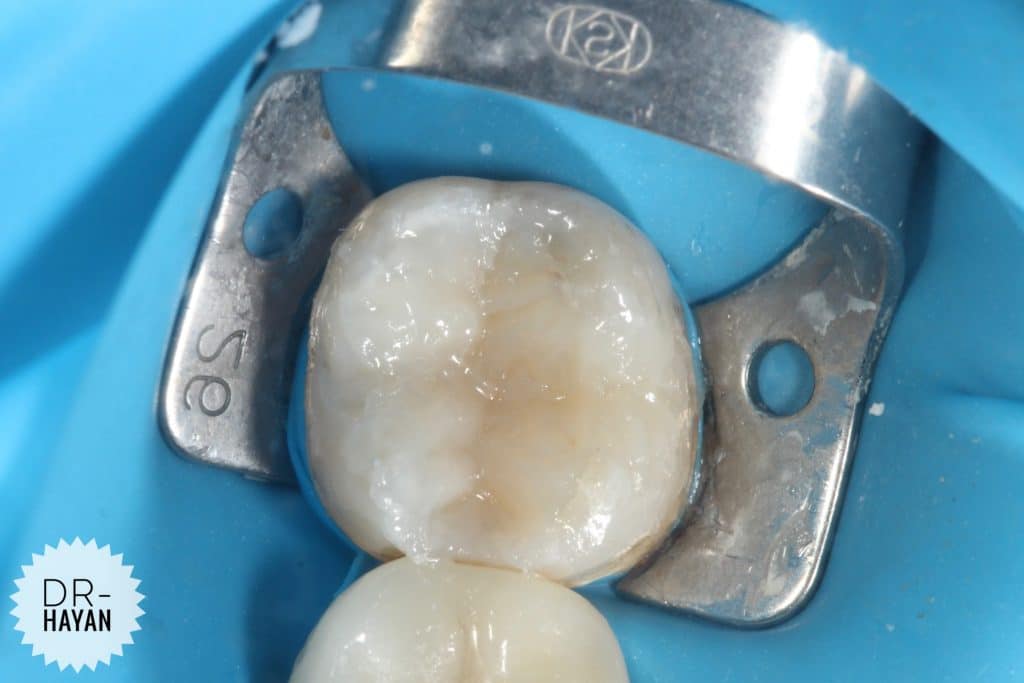

Finishing the floor And

Remove any sharp angle

After that

IDPC

Selective etch

- finishing the gingival seat by sharp excavator

- After etching dis infected the cavity by CHX

And dry it only